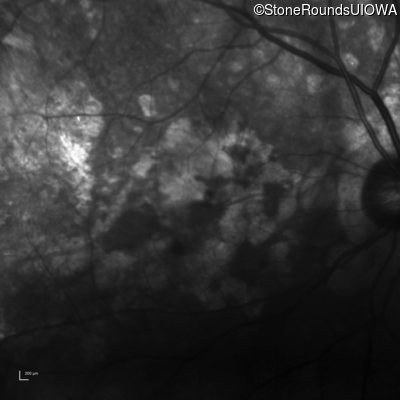

Infrared Fundus Photograph - Right - 20/200 +2

Exemplar